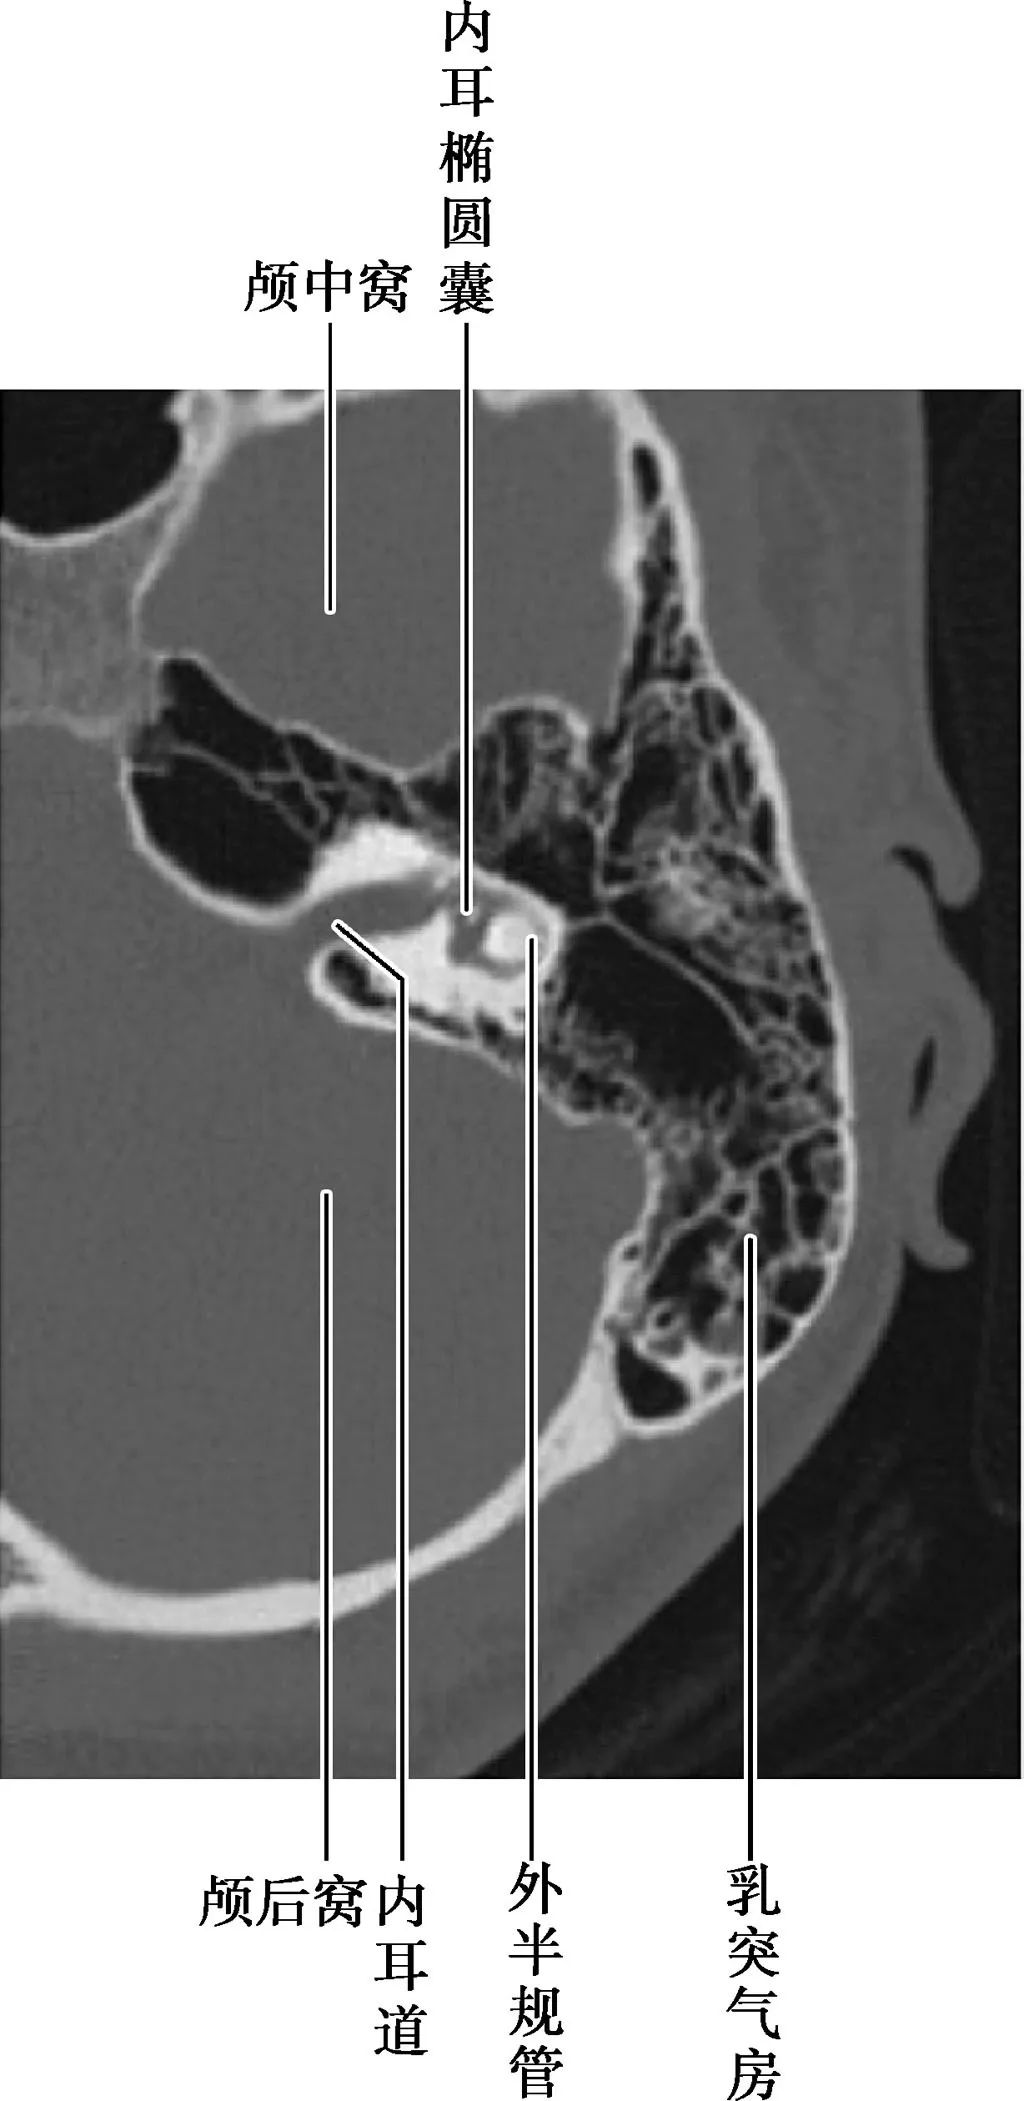

局部结构

(薄层CT)

(CT矢状面)

A.耳蜗层面;B.前庭层面;C.面神经管乳突段层面1.颈静脉球;2.内耳道;3.耳蜗;4.前庭导水管;5.后骨半规管;6.总骨脚;7.上骨半规管;8.前庭;9.面神经管迷路段;10.鼓膜张肌;11.圆窗;12.外骨半规管;13.砧骨长脚;14.锤骨颈;15.面神经管乳突段